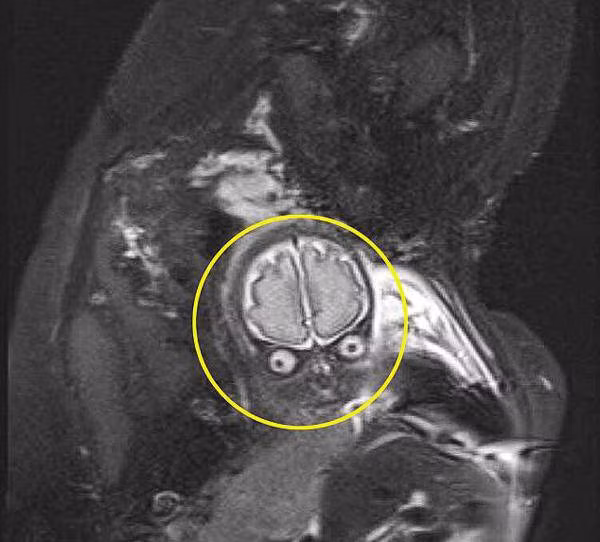

"Lúc đầu mọi chuyện diễn ra bình thường nhưng sau đó con bắt đầu quay mặt lại nhìn tôi và khiến tôi hết hồn. Trên màn hình siêu âm hiện ra hình ảnh như một chiếc đầu lâu và nó ngày càng to, rõ ràng hơn. Tôi sững người và bật thốt lên rằng: Đây không phải con tôi, có gì nhầm lẫn không", Jessica kể lại.

Sau đó, bác sĩ siêu âm trấn an bà mẹ rằng đôi khi hình ảnh siêu âm đen trắng sẽ vô tình tạo nên hình ảnh đáng sợ nên cô không cần lo lắng.

Ảnh chụp MRI như người ngoài hành tinh do một cặp vợ chồng người Anh chia sẻ.